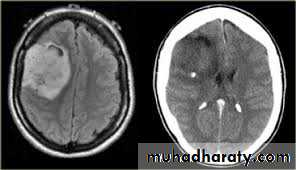

Meningioma

CT finding

meningioma presented as isodense area or slightly hyper density area with surrounded crescent of hypo density ( csf cap ) post contrast injection the lesion enhance homogeneously with enhancing Dural tail .

20 % show calcification